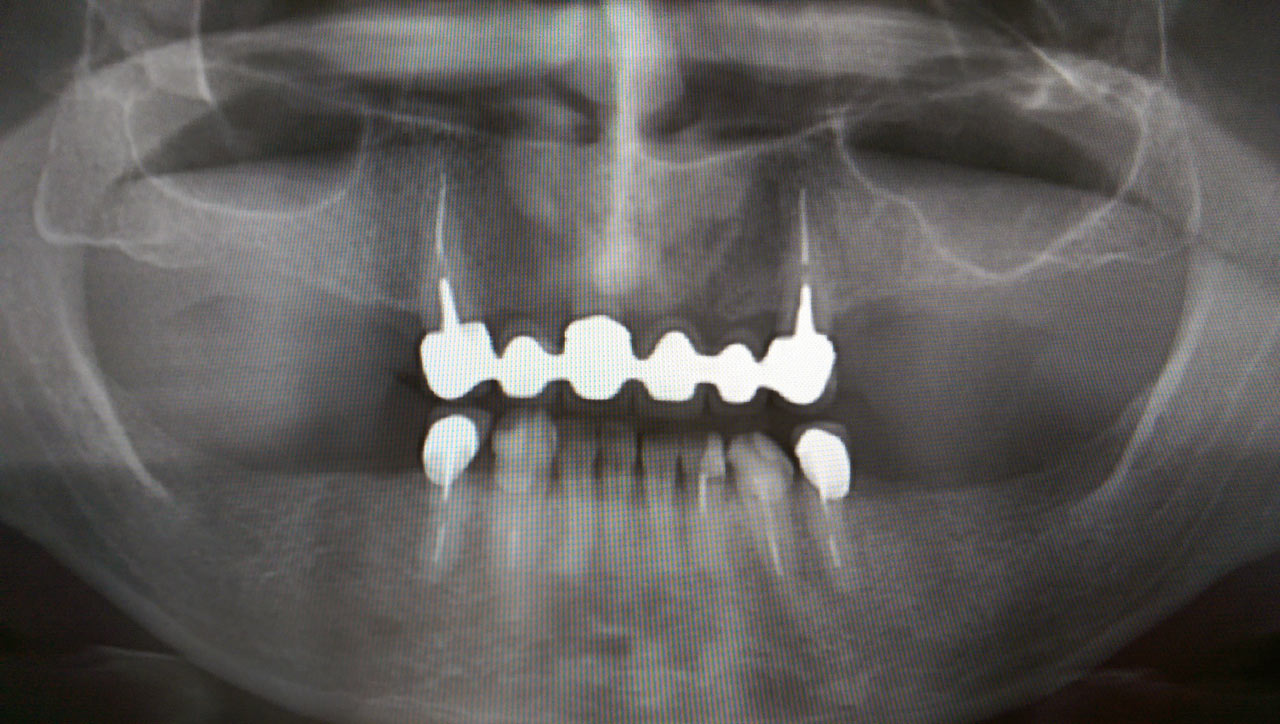

Teljes alsó,felső állcsont helyreállítása azonnal

terhelhető implantátumokkal és porcelán hidakkal.

Rágófunkció esztétikus helyreállítása azonnalterhelhető svájci IHDE implantátumokkal és porcelán koronákkal.

A régóta fennálló foghiány és a mozgó fogak miatt a páciens nem tudott jól rágni és harapni, illetve mosolyogni sem mert már jó ideje. A leggyorsabb és a legesztétikusabb megoldás az ilyen esetekre az IHDE azonnal terhelhető implantátumok behelyezése, és az azokra rögtön elkészített porcelán koronák elkészítése.

A teljes munka - az implantáció, a végleges koronák elkészítése - 5 munkanapot vett igénybe.